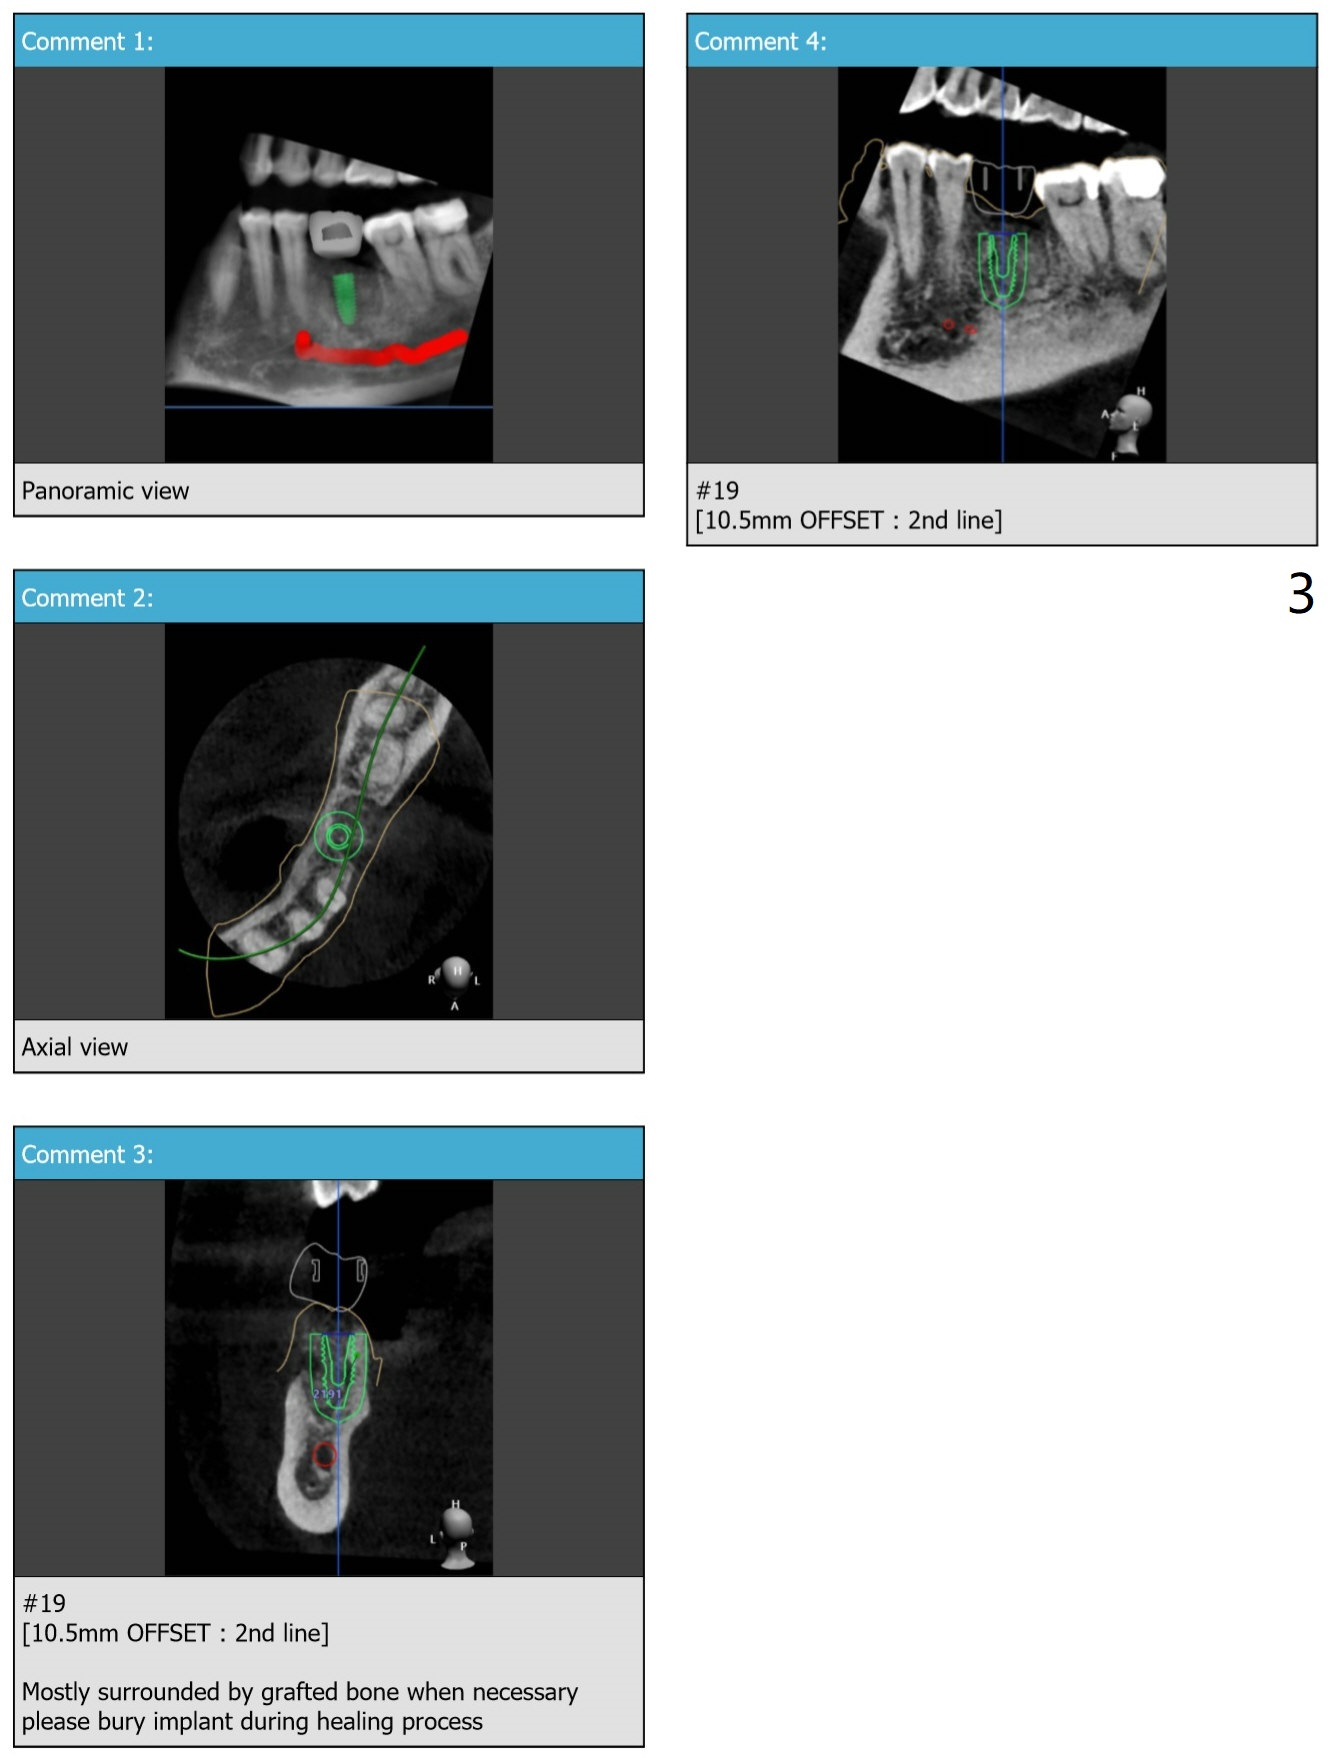

Buccal Plate Collapse: Lingual Placement

Return to Lower Molar Immediate Implant, Trajectory II